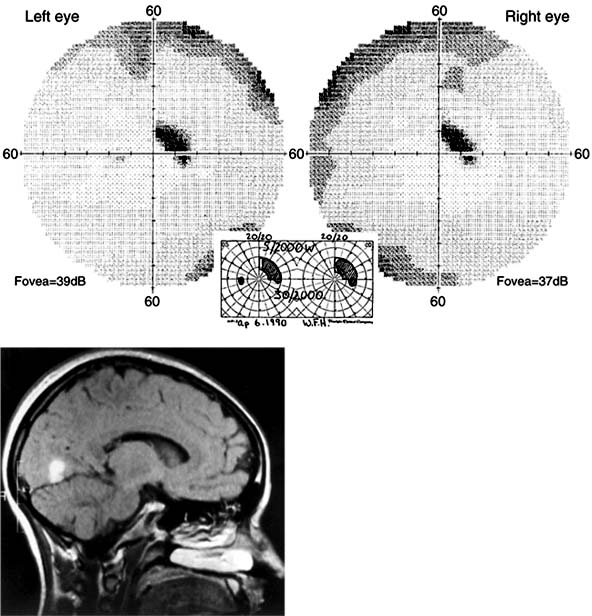

Figure 14-4

Figure 14-4: Occipital lobe abscess. Top: Automated perimetry and tangent screen examination showing homonymous, congruous, paracentral scotoma in right upper visual fields. Bottom: Parasagittal MRI showing lesion involving left inferior calcarine cortex. (Reproduced, with permission, from Horton JC, Hoyt WF: The representation of the visual field in human striate cortex. A revision of the classic Holmes map. Arch Ophthalmol 1991;109:816.)

Figure 14-5

Figure 14-5: Bilateral occipital infarcts with bilateral macular sparing. Top: Tangent screen and superimposed Goldmann visual fields of both eyes showing bilateral homonymous hemianopia with macular sparing, greater in the right hemifield. Bottom: Axial MRI showing sparing of occipital poles. (Reproduced, with permission, from Horton JC, Hoyt WF: The representation of the visual field in human striate cortex. A revision of the classic Holmes map. Arch Ophthalmol 1991;109:816.)